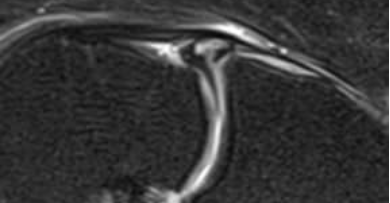

초음파로 보는 알짜근육학, 319p

위 사진은 제가 집필한

영상입니다.

한의학의 음시, 양구혈을

초음파로 관찰하면

대퇴사두근 슬개골 부착부와

관절낭과 연결된 주머니(recess)가

이렇게 정상적으로 보여야 합니다.

양구혈의 경혈 초음파 영상